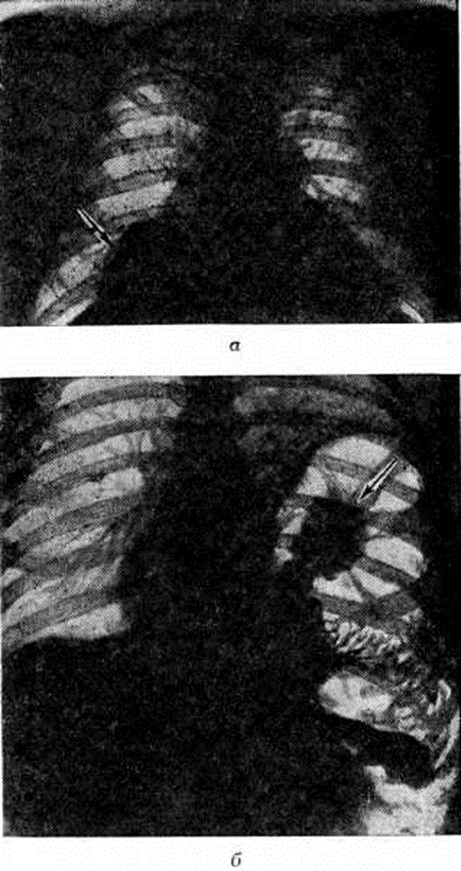

Рис

Рентгенограммы (прямая проекция) грудной клетки больных с торакоабдоминальными повреждениями: а — при правостороннем повреждении; в правой плевральной полости тень перемещенной печени (указана стрелкой); б — при левостороннем повреждении; в левой плевральной полости тень контрастированного желудка (указана стрелкой).

Постановка диагноза Торакоабдоминальные повреждения затруднена. По данным Д. А. Арапова и Н. В. Хорошко (1970), правильный предоперационный диагноз устанавливался у 66,7% раненых с Торакоабдоминальные повреждения Диагностика открытых Торакоабдоминальные повреждения несколько облегчается наличием раневых отверстий, которые иногда могут служить ориентиром для определения хода раневого канала. В этих случаях достоверным признаком Торакоабдоминальные повреждения являются симптомы проникающего ранения груди при локализации раны в области живота и комплекс абдоминальных симптомов при локализации раны в области груди. Еще труднее диагностика закрытых Торакоабдоминальные повреждения Существенную помощь в диагностике оказывают данные рентгенологическое исследования, при котором выявляются признаки пролабирования органов брюшной полости в плевральную полость (рисунок), наличие газа под куполом диафрагмы, ограничение подвижности и высокое стояние диафрагмы и другие